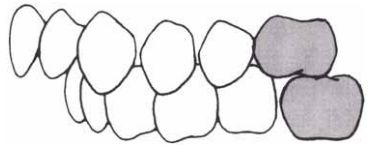

19 如下圖所示,此種上下顎第一大臼齒間的關係屬下列何種咬合分類? (A)安格氏一級 (B)安格氏二級 (C)安格氏三級 (D)安格氏四級